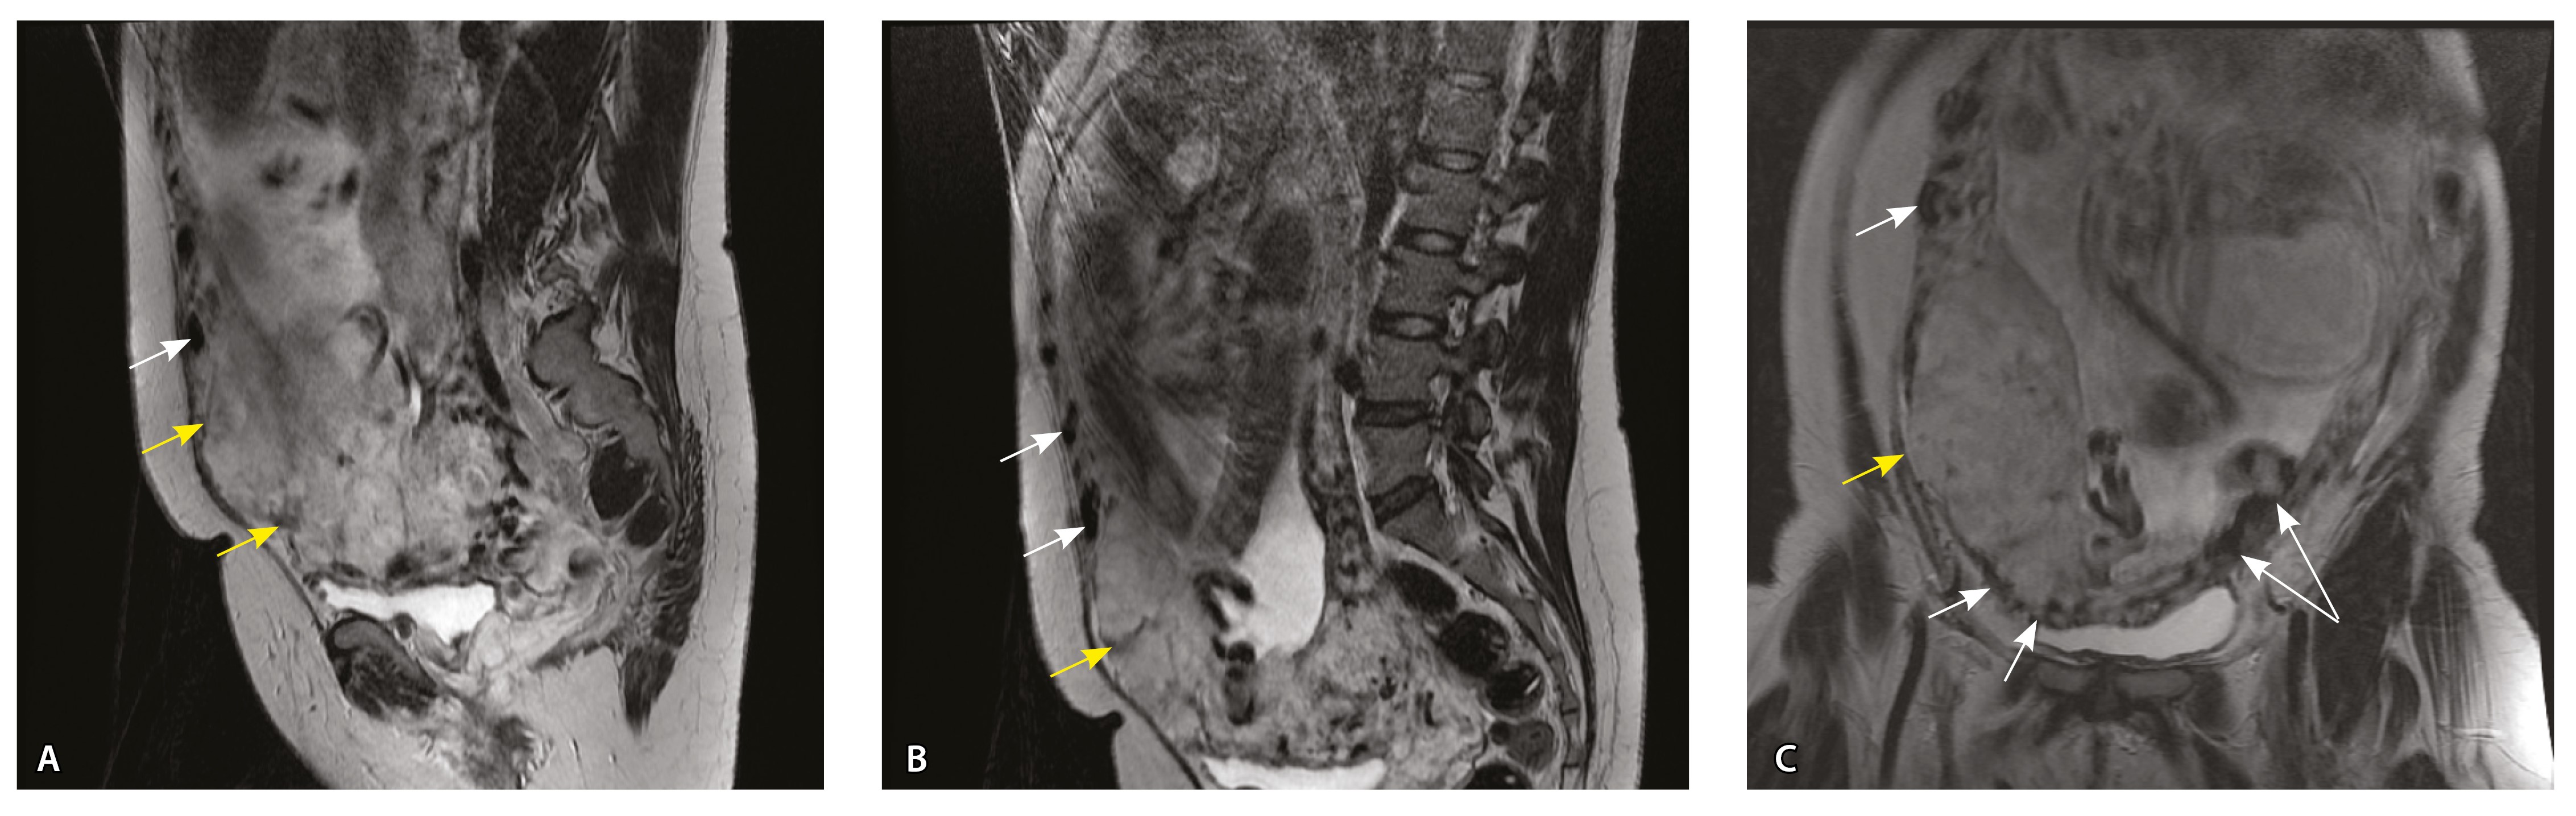

Сосуды 5-го типа. Наличие гиперваскуляризации за пределами матки по данным МРТ, на границе с мочевым пузырем с вовлечением его стенки, сосуды в области перешейка матки, параметрия, в том числе в сочетании с признаками фиброза, наличием рубцово-спаечных изменений и др. Можно предположить, что сосуды 5-го типа являются аналогом pl. рercreta PAS 3b, 3c (рис. 15).

Рис. 15. Беременность 34 недели, pl. percreta, PAS 3b по FIGO (A, Б), PAS 3c по FIGO (В). На магнитно-резонансных томограммах в режиме Т2-взвешенного изображения в сагиттальной (A, В) и аксиальной (Б) плоскостях определяется гиперваскуляризация в области выраженно истонченного нижнего маточного сегмента с распространением сосудов на заднюю стенку мочевого пузыря в области дна (белые стрелки), в область перешейка матки (желтые стрелки)

Данный вариант в патоморфологической картине наиболее сложен для оценки ввиду того, что такие структуры, как параметрий, перешеек матки, стенка мочевого пузыря, обычно не предоставляются в виде макропрепаратов, поэтому визуальные методы, в частности МРТ, могут с большей точностью оценить вовлеченность смежных структур. На микропрепаратах данный вариант инвазии плаценты сочетается с рубцово-спаечными изменениями задней стенки мочевого пузыря с нижним маточным сегментом (рис. 16).